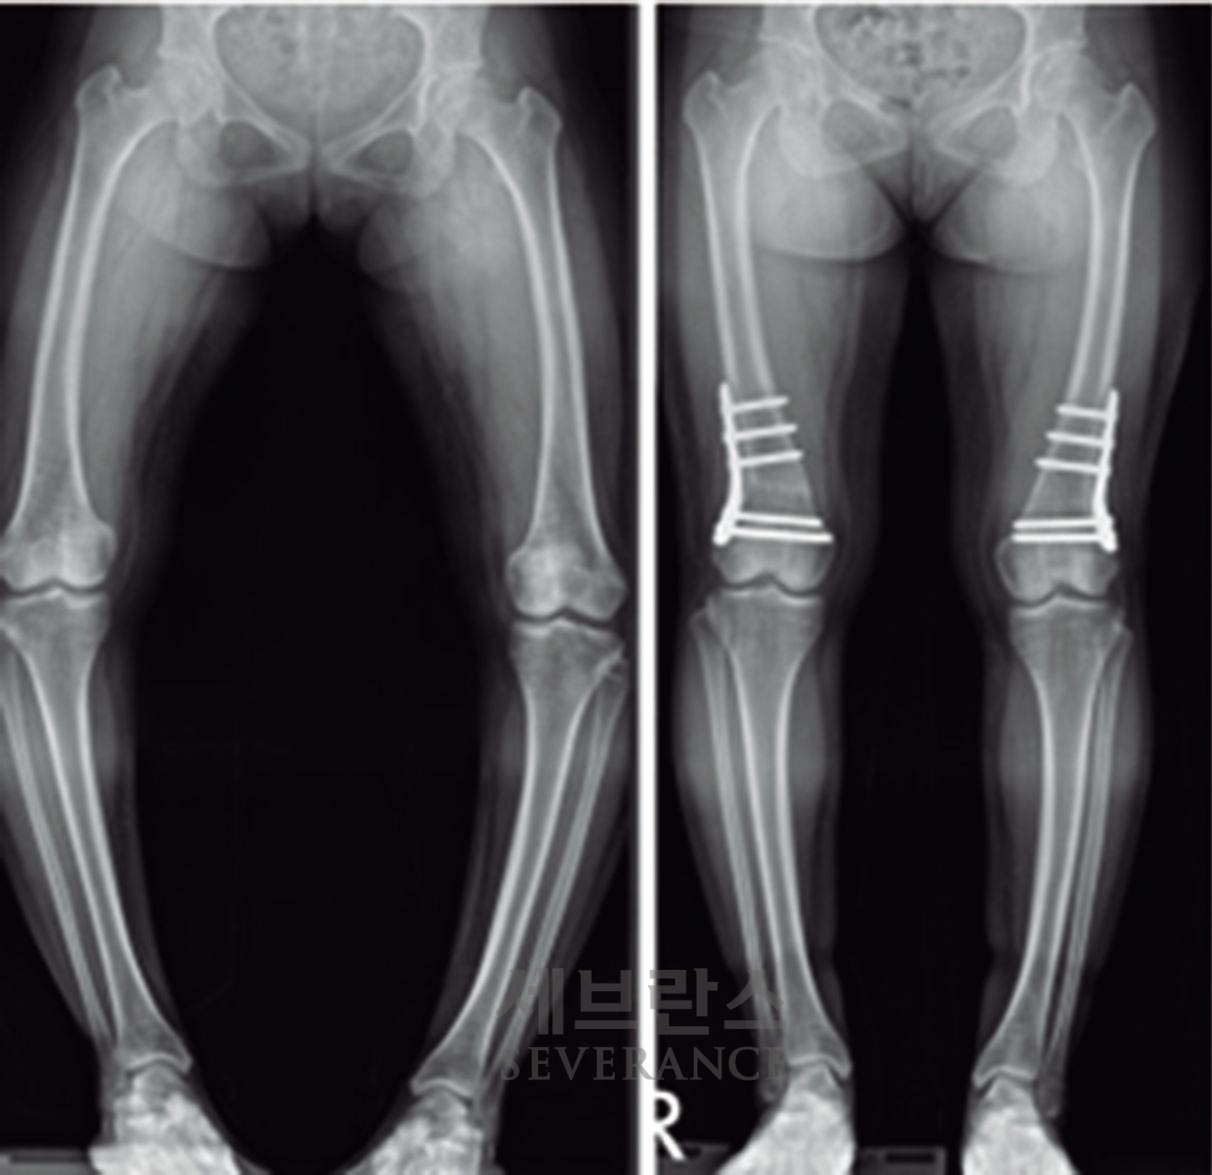

• 성장조절술

성장판이 열려 있는 아이에게 많이 사용되는 성장조절술은 한쪽 성장판의 성장을 일시적으로 억제해 시간이 지나면서 다리 길이나 각도가 서서히 교정되도록 하는 방법입니다. 일반적으로 심하지 않은 O다리나 X다리, 경미한 다리 길이 차이에 적용합니다. 흉터가 작고 회복이 빠르지만, 효과가 나타나기까지 시간이 필요하고 성장이 끝난 아이에게는 사용할 수 없습니다. 또 교정이 완료된 후에도 성장 과정에서 일부 각도가 다시 돌아오는 ‘성장 반동’ 현상이 나타날 수 있습니다. 따라서 성장판이 완전히 닫힐 때까지 정기적으로 추적 관찰을 받아야 합니다.

특발성 대사성 질환으로 인한 외반슬(X다리)에서 성장조절술을 시행한 환아성장판